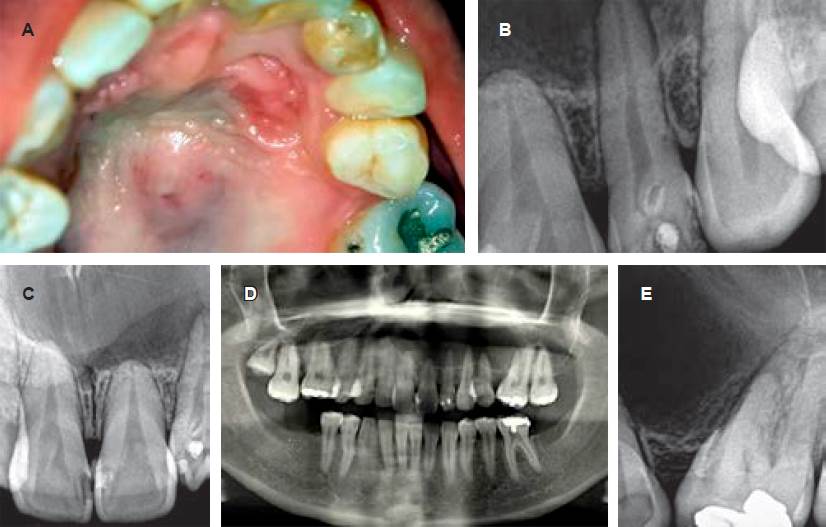

Al examen intraoral, se observó una región inflamada en el paladar duro, algo lateralizada hacia la izquierda, fluctuante, con tendencia a la supuración y dolorosa a la palpación. El diagnóstico provisional fue de absceso palatino, evidenciándose el incisivo lateral superior derecho con una coloración grisácea, test de excitabilidad pulpar negativo y sospecha clínica de necrosis pulpar. Al examen radiográfico (técnica periapical), se observó una gran lesión radiolúcida corticalizada que se extendía de las áreas confinadas a la pieza problema (Figura 1). Además, como hallazgo radiográfico de relevancia, se observó a nivel del límite amelocementario una zona de radiodensidad similar a la dentina, asociada a una invaginación de tejido dentario circunscripta por un área radiopaca compatible con DI. Con el objetivo de evidenciar con mayor nitidez esta lesión, se indicaron ortopantomografía y tomografía axial computarizada. En ellas se observó una gran lesión lítica que ocupaba casi la totalidad del hemimaxilar superior izquierdo sin llegar a comprometer fosas nasales y seno maxilar, cuyo límite anterior se encontraba en el sector correspondiente a incisivos centrales y su límite posterior estaba delimitado por el primer molar izquierdo. Asimismo, se evidenciaba osteólisis del hueso maxilar y palatino. La Figura 2 ilustra los diferentes cortes tomográficos, los cuales permiten observar la imagen osteolítica compatible con el proceso quístico. Todas las piezas involucradas mostraron ausencia de signos de rizólisis patológica y conservaban la vitalidad pulpar, excepto el incisivo lateral superior izquierdo involucrado, con la imagen de DI. El diagnóstico clínico fue quiste maxilar inflamatorio asociado a necrosis pulpar proveniente de incisivo lateral superior.

Figura 1 Características clínico-radiográficas del caso. A) Se observa sobre la bóveda palatina una lesión discretamente elevada, con superficie eritematosa y zonas azulinas, en la cual durante las maniobras de palpación se podía evidenciar fluctuación y un contenido líquido. Estas maniobras generaban intenso dolor y sensación de opresión en la zona. Además, es importante observar la morfolog lóbulo palatino de gran tamaño, asemejándose a la corona clínica de un premolar. B) Imagen radiográfica de dens invaginatus ía dentaria de la corona y la coloración del incisivo lateral, donde se puede evidenciar un coronario en el incisivo lateral superior izquierdo y una zona de rarefacción ósea en el ápice radicular. C) Imagen radiográfica sector anterior de incisivos centrales, donde se puede observar una imagen radiolúcida que involucra dichas piezas dentarias, separadas del tejido óseo normal circundante por una discreta línea radiopaca. D) En la ortopantomografía, obsérvese una imagen osteolítica que abarca el hemimaxilar izquierdo. E) En esta imagen radiográfica se puede observar el límite posterior de la lesión osteolítica con una zona radiolúcidaquellegaagenerardesplazamientodentariodel primer molar superior izquierdo.